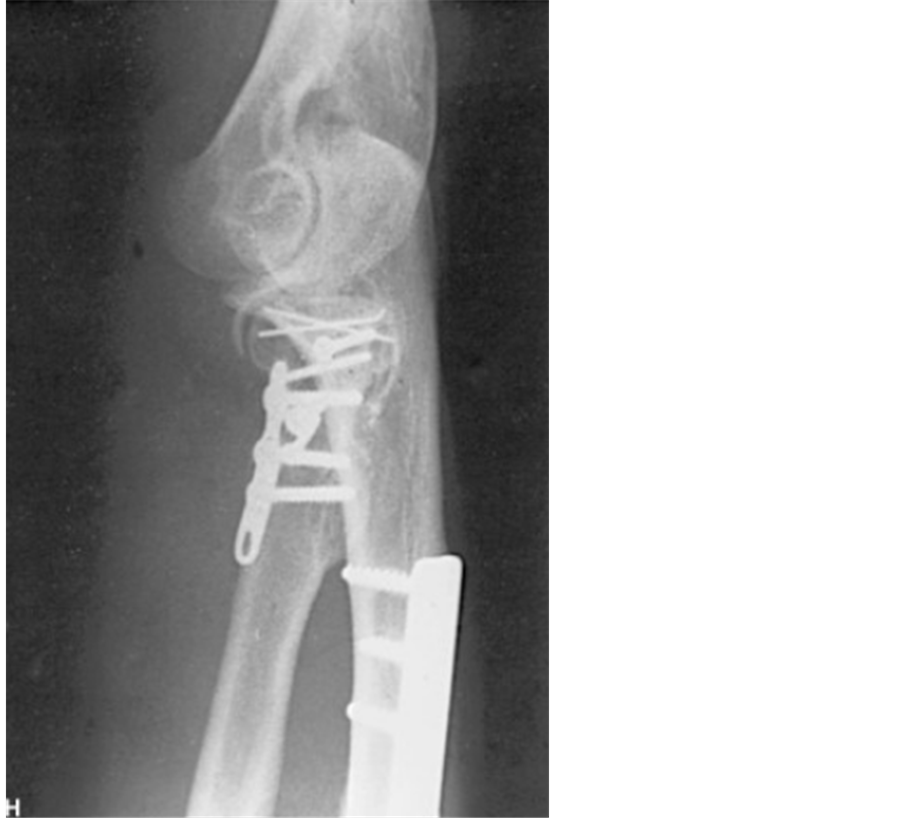

In the operating room, Under balanced general anesthesia, closed reduction with external maneuvers were made for both wrists dislocations. Controlled by fluoroscopy, The local temperature and color conditions improved and then an orthopedic treatment was made with cast immobilization for both wrists seeing the stability of the reduction (Figure 4 and Figure 5). Surgical treatment of the elbow before reduction of its dislocation with mini plate for the radial head and a plate of the ulnar shaft (Figure 6).

Figure 6. Right elbow after treatment.